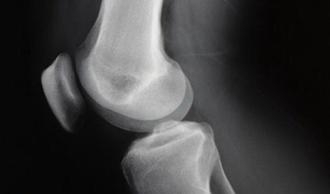

parameniscitis rodilla

Es una de las lesiones de rodilla más frecuentes. Se trata de la inflamación del paramenisco; esto es, el área que rodea el menisco en la rodilla. El menisco es un cartílago que sirve de separador entre los huesos fémur y tibia, protegiendo las superficies de la articulación, estabilizándola y amortiguando los impactos. La rodilla se mueve con dificultad, mayor cuanto peor es la lesión.